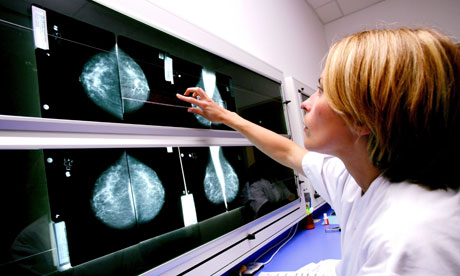

Παράλληλα, Βρετανοί επιστήμονες ανακάλυψαν μια νέα πρωτεΐνη, που εμπλέκεται άμεσα στην αντίσταση που προβάλλει ο οργανισμός στα φάρμακα για τον καρκίνο του μαστού . Η ομάδα με Έλληνα μάλιστα επικεφαλής, ανοίγει το δρόμο για νέου τύπου φάρμακα ενάντια στη νόσο.